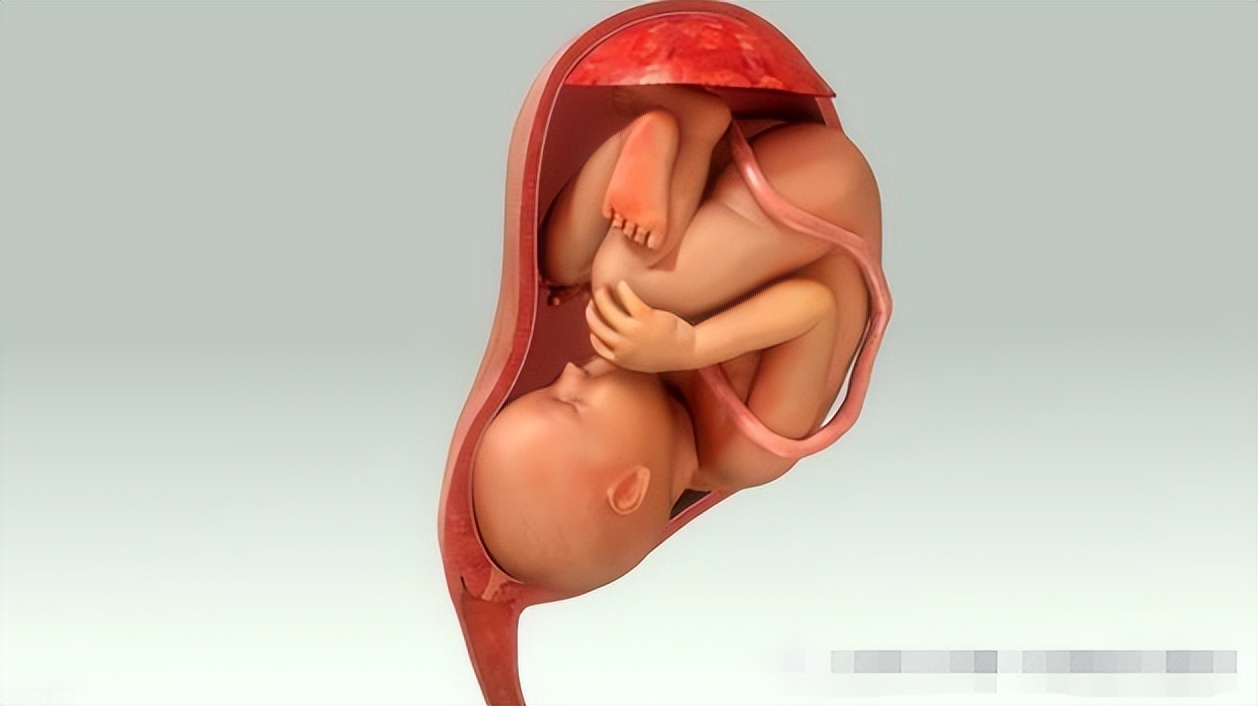

孕育生命的小房子,每个生命来到世界上的第一个「家」,更是女性青春和魅力的守护者,但以子宫肌瘤、子宫腺肌病为代表的高发妇科疾病,给广大女*生活性**带来诸多困扰。

它是在超声监控下完成的,定位准确,只针对病灶进行消融治疗,且没有辐射,不会伤及子宫及周围正常组织器官,是 有生育要求的子宫肌瘤及子宫腺肌病患者 很好的一种治疗选择。目前已有不少子宫肌瘤及腺肌病患者在使用海扶刀治疗后成功怀孕生产的案例。